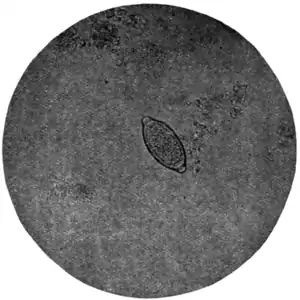

Fig. 170.—Ovum of Trichiuris trichiura, x 280. (Photograph by Dr. J. Bell.)